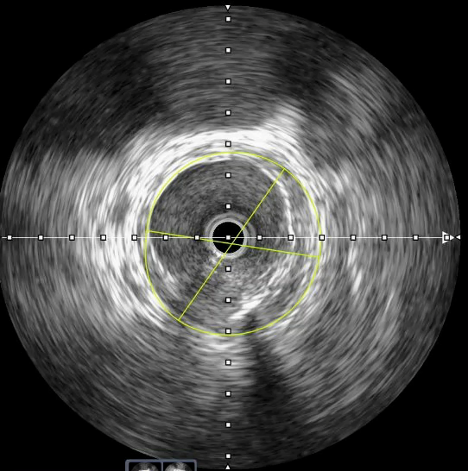

The occlusion was successfully crossed with a guidewire (Videos 1-3). Intravascular ultrasound (IVUS) was utilized to evaluate vessel morphology and size, and guide precise stent placement. IVUS from the distal to proximal SFA revealed a distal luminal area of approximately 6.0 mm² and significant calcific burden (Figure 1). Sequential PTA with 5.0 mm and 6.0 mm balloons was performed, followed by successful deployment of a 6.0 mm x 150 mm self-expanding stent. Post dilatation was done with a 6.0 mm balloon (Videos 4-5).